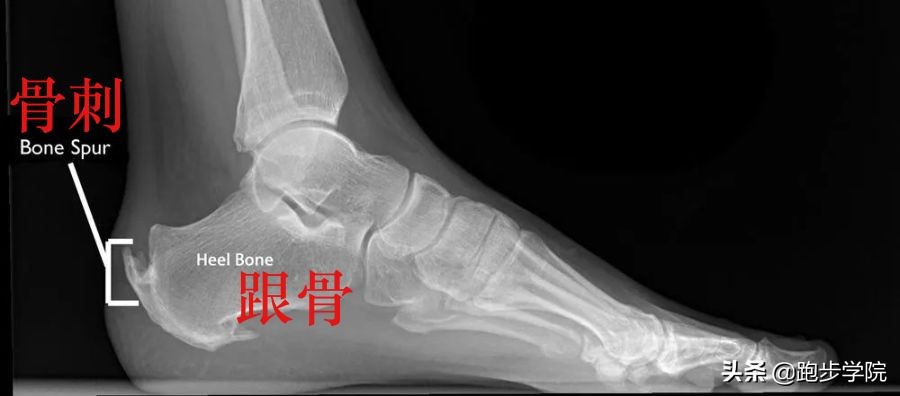

另外,在年纪较大的运动者中,经常出现的是 止点跟腱炎。患有这种跟腱炎的运动者通常会在跟骨位置出现疼痛,并在运动后会有疼痛加重的情况。随之而来的是,跟腱附着点炎症病变,肌腱会出现钙化转变为骨质,也就是我们常说的“骨刺”。

骨刺(photo via Bouldercentre for Orthopedics&Spine)